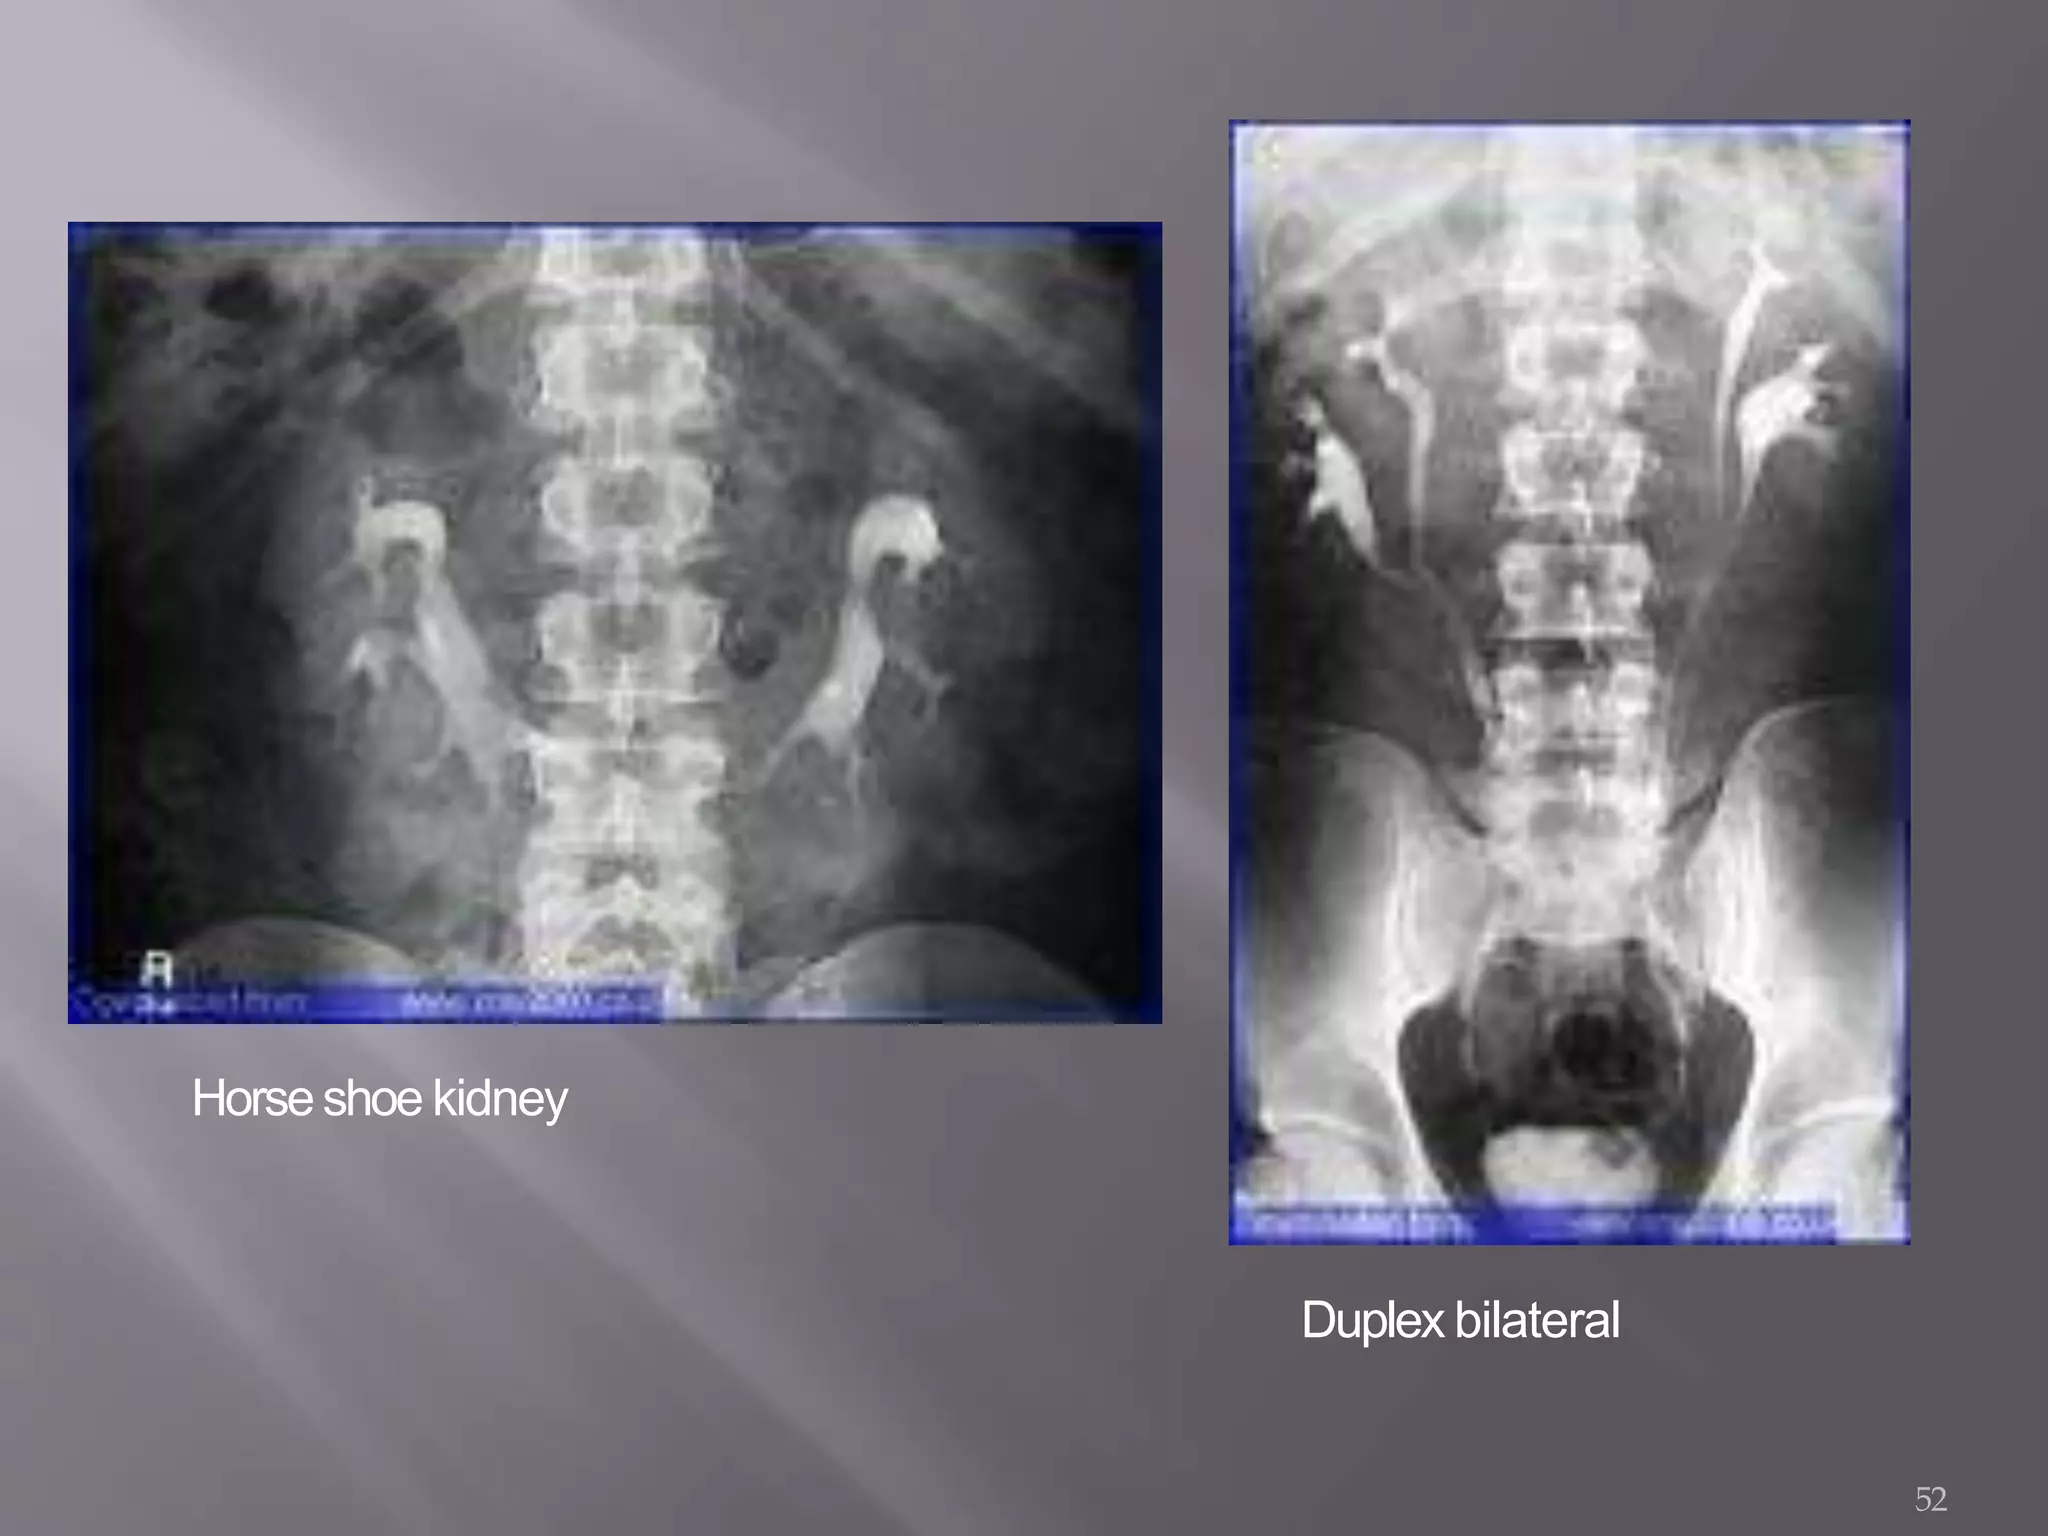

Horse shoe kidney Lower pole-

parenchymal fusion

Kidney malrotation

and possible

nephrogram

demonstrating

Duplication More than onerenal

pelvis or ureter

Double renal pelvis

in single kidney;two

ureters exit kidney

and empty into

bladder.

Horseshoe kidney

52

Duplex bilateral